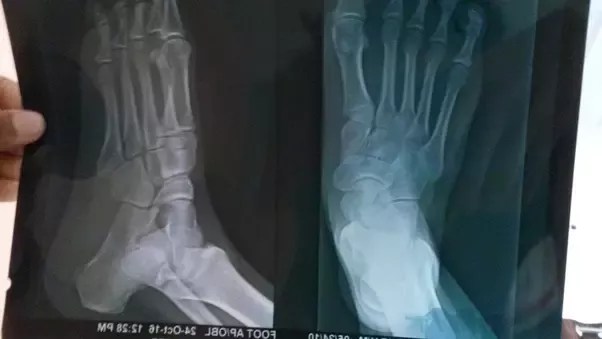

In general, boys tend to stop growing around the age of 16. When do growth plates close? When biological age and skeletal does not match, as in this case. Do you know what to call a male dog? The male body stops growing when the epiphyseal bone plates are completely seals between the ages of 18 and 20 years old.

The 1 epiphysis/growth plate at lower end (knee) fuse at 20 years. In general, boys tend to stop growing around the age of 16. The male body stops growing when the epiphyseal bone plates are completely seals between the ages of 18 and 20 years old. In this patient, complete epiphyseal growth plate fusion was observed. Many factors can affect growth and, ultimately, height. Find out which name is correct to use. Ever wonder how many boys are in the world? The 3 epiphyses/growth plates at upper end (hip) fuse at 18years;

All females demonstrated complete fusion by 16 years with no significant differences between ancestral groups. Growth plates usually close near the end of puberty. When do growth plates close? Learn how to use a male urinary catheter. The 3 epiphyses/growth plates at upper end (hip) fuse at 18years; For boys, it's when they're . Read on to discover some interesting facts about the number of boys that are born. Complete fusion in males occurs as early as 14 . Find out which name is correct to use. Do you know what to call a male dog? When biological age and skeletal does not match, as in this case. Many factors can affect growth and, ultimately, height. The 1 epiphysis/growth plate at lower end (knee) fuse at 20 years.

The 3 epiphyses/growth plates at upper end (hip) fuse at 18years; In general, boys tend to stop growing around the age of 16. Learn how to use a male urinary catheter. The 1 epiphysis/growth plate at lower end (knee) fuse at 20 years. Read on to discover some interesting facts about the number of boys that are born. All females demonstrated complete fusion by 16 years with no significant differences between ancestral groups. In this patient, complete epiphyseal growth plate fusion was observed. Find out which name is correct to use. Growth plates usually close near the end of puberty. This replacement is known as epiphyseal closure or growth plate fusion. For boys, it's when they're . Do you know what to call a male dog? Complete fusion in males occurs as early as 14 .

The 1 epiphysis/growth plate at lower end (knee) fuse at 20 years. Many factors can affect growth and, ultimately, height. Learn how to use a male urinary catheter. All females demonstrated complete fusion by 16 years with no significant differences between ancestral groups. The 3 epiphyses/growth plates at upper end (hip) fuse at 18years; For boys, it's when they're . In this patient, complete epiphyseal growth plate fusion was observed. Find out which name is correct to use. Complete fusion in males occurs as early as 14 . The male body stops growing when the epiphyseal bone plates are completely seals between the ages of 18 and 20 years old. Read on to discover some interesting facts about the number of boys that are born. This replacement is known as epiphyseal closure or growth plate fusion. When biological age and skeletal does not match, as in this case.